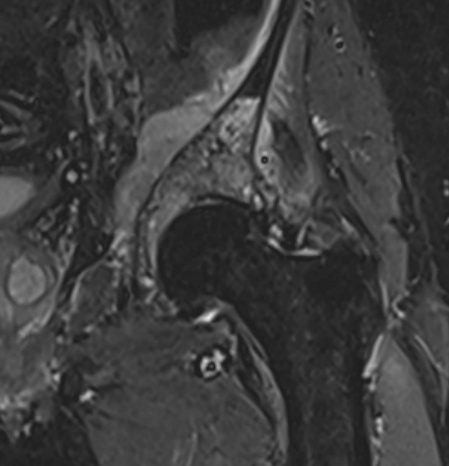

MRI

- MRI of 179 chondrosaroma

- features of high grade chondrosarcoma

- bone expansion, active periostitis, soft tissue mass and increased tumour length